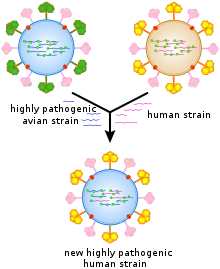

Because of the absence of RNA proofreading enzymes, the RNA-dependent RNA polymerase that copies the viral genome makes an error roughly every 10 thousand nucleotides, which is the approximate length of the influenza vRNA. Hence, the majority of newly manufactured influenza viruses are mutants; this causes antigenic drift, which is a slow change in the antigens on the viral surface over time.[78] The separation of the genome into eight separate segments of vRNA allows mixing or reassortment of vRNAs if more than one type of influenza virus infects a single cell. The resulting rapid change in viral genetics produces antigenic shifts, which are sudden changes from one antigen to another. These sudden large changes allow the virus to infect new host species and quickly overcome protective immunity.[65] This is important in the emergence of pandemics, as discussed below in the section on epidemiology. Also, when two or more viruses infect a cell, genetic variation may be generated by homologous recombination.[79][80] Homologous recombination can arise during viral genome replication by the RNA polymerase switching from one template to another, a process known as copy choice.[80]

New influenza viruses are constantly evolving by mutation or by reassortment.[41] Mutations can cause small changes in the hemagglutinin and neuraminidase antigens on the surface of the virus. This is called antigenic drift, which slowly creates an increasing variety of strains until one evolves that can infect people who are immune to the pre-existing strains. This new variant then replaces the older strains as it rapidly sweeps through the human population, often causing an epidemic.[194] However, since the strains produced by drift will still be reasonably similar to the older strains, some people will still be immune to them. In contrast, when influenza viruses reassort, they acquire completely new antigens—for example by reassortment between avian strains and human strains; this is called antigenic shift. If a human influenza virus is produced that has entirely new antigens, everybody will be susceptible, and the novel influenza will spread uncontrollably, causing a pandemic.[195] In contrast to this model of pandemics based on antigenic drift and shift, an alternative approach has been proposed where the periodic pandemics are produced by interactions of a fixed set of viral strains with a human population with a constantly changing set of immunities to different viral strains.[196]